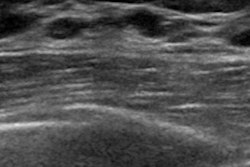

The technology shows promise for reducing the operator variability and subjectivity of handheld ultrasound. But some have expressed concern that the time required to interpret ABUS exams may negatively influence workflow.

To investigate the issue, Huppe and colleagues conducted a study that included 99 women with BI-RADS breast density classifications of C ("heterogeneously dense") or D ("extremely dense") who underwent both a digital screening mammogram and an ABUS screening exam between 2013 and 2014. Three radiologists with varying levels of experience read all of the ABUS exams. The researchers recorded interpretation times and the readers' final interpretations.